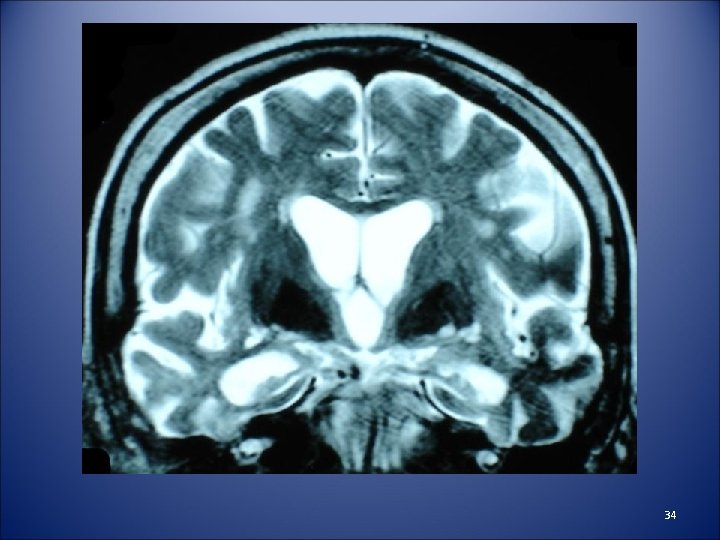

34